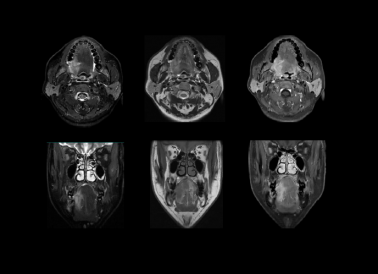

原理先容:口腔颌面部、喉部主要由肌肉、脂肪、血管、淋巴组织、腺体、骨组织及神经组成。 MRI 具有很是高的软组织比照度,可显示特征性信号强度,故MRI比螺旋 CT能提供更多的诊断信息

临床用途:腮腺区肿瘤、舌和口底区肿瘤、颌面深部间隙区恶性肿瘤、颞下颌枢纽杂乱综合征、鼻咽癌